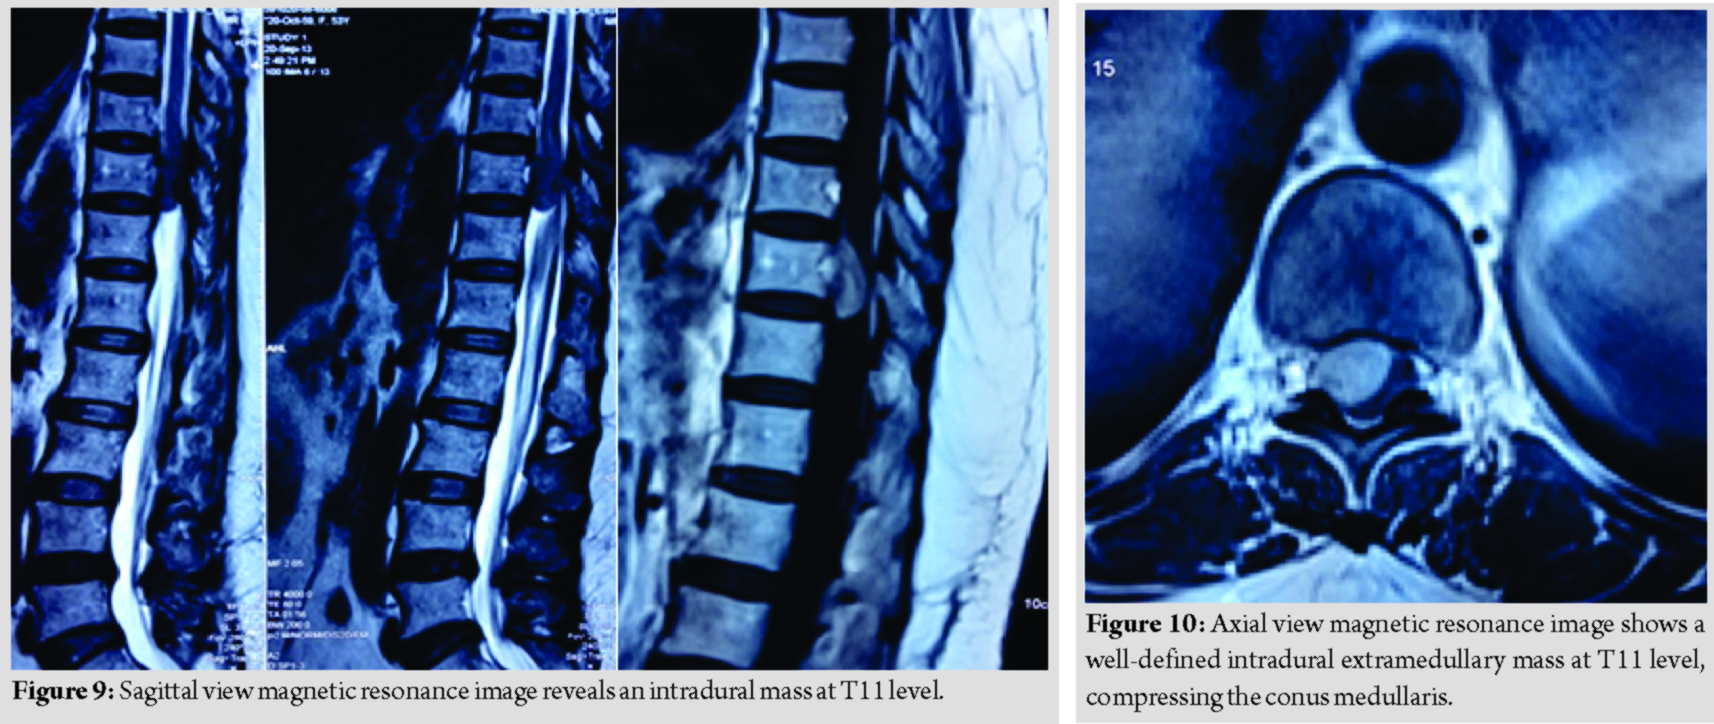

A 53-year-old lady presented with complaint of back pain and bilateral lower limb weakness for a year duration, associated with urinary incontinence for 2 months duration. Examination reveals normal tone, power over the right lower limb was more affected (MRC Grade 2) as compared to the left lower limb (MRC Grade 3), lower limb reflexes were brisk, and sensation was reduced from T11 dermatome onward. Magnetic resonance imaging reveals a well-defined intradural extramedullary mass at T11, compressing on the conus medullaris (Fig. 9 and 10).

She underwent laminectomy of T10 and T11 with microscopic assisted excision of the tumor. The mass was successfully removed completely without sacrificing the involved nerve root (Fig. 11 and 12).

Her neurological recovery was remarkable despite being symptomatic for a year duration. By post-operative day 2, she claims that her back pain has completely resolved. She regained bladder control at 1-week post-operative and was ambulating with aid. At 2 weeks post-operative, she was able to ambulate without aid. Final diagnosis was confirmed through histopathology. None of these patient suffered from neurofibromatosis. No instrumentation was done to stabilize the spine as only a single-level laminectomy was involved. The surgeon took careful measures to ensure the facet remains untouched and thereby maintaining the stability of the spine. These patients have followed up for the past 7 years with no progressive kyphosis noted or clinical symptoms and signs suggesting recurrence.